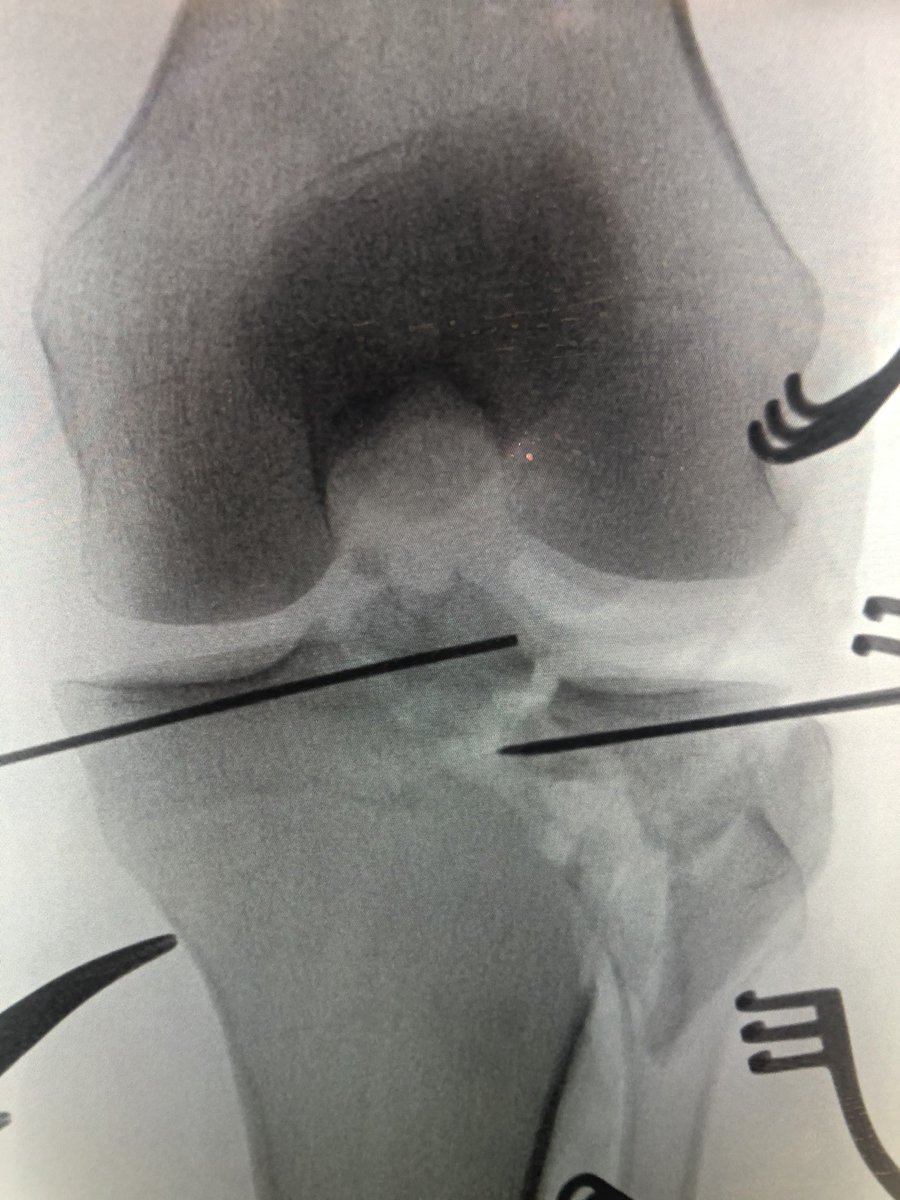

[1/6] Tibial plateau with eminence fracture. The Xrays show you the breaks in the plateau but also that the eminence seems odd somehow. This is more complex than it appears at first glance.

[2/6] CT gives you lots of info including comminution in the weightbearing lateral surface, and also the eminence fracture (arrow). Because of how medial this was, I planned for a femoral distractor. Make sure to limit your distraction time due to risk to peroneal nerve.